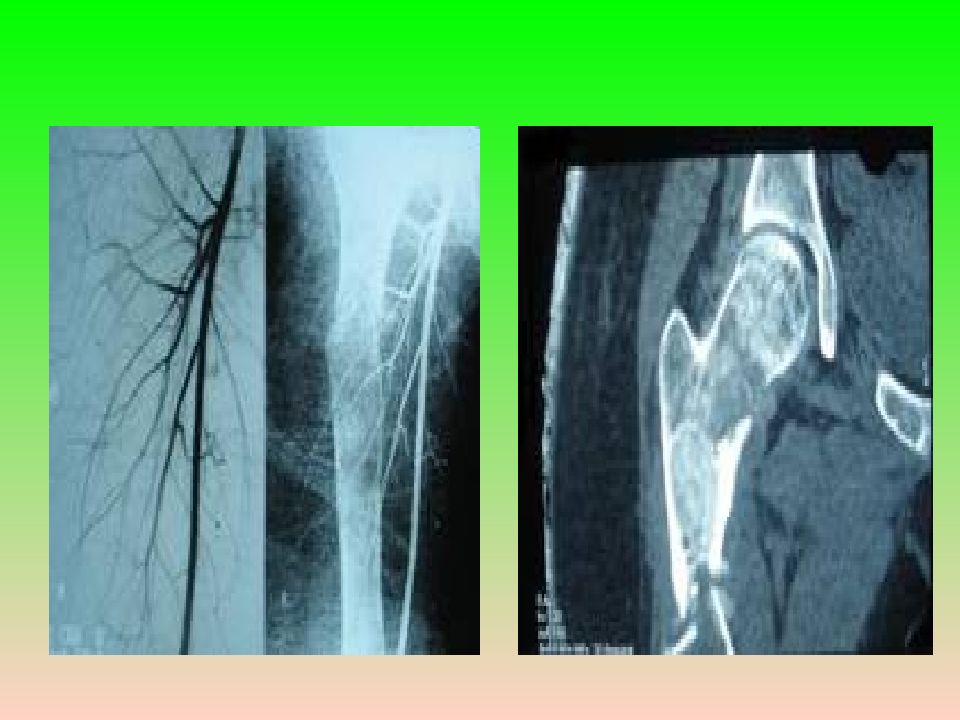

Слайд 8: Клиническая картина

Боли различной интенсивности, искривление и деформация костей, патологические переломы.  Рентгенологически — литическое поражение с чёткими контурами и склерозированными краями; может быть вздутие кости, патологический перелом. Клиническая картина

Слайд 11: Патоморфология

Макроскопически — плотная ткань бело-серого цвета с мелкими включениями костной плотности. Патологическая ткань почти всегда располагается только внутри костномозгового канала. Патоморфология